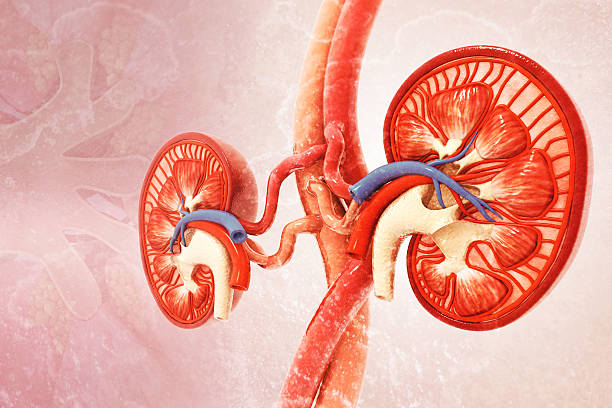

Kidneys are metabolically active organs. They process toxins, regulate pH, balance electrolytes, and manage waste — all while being exposed to oxidative stress every single day. This makes them especially vulnerable to free radical damage, inflammation, and gradual cellular breakdown.

Among these nutrients, antioxidants play a central role. Oxidative stress accelerates kidney decline by damaging nephrons (the kidney’s filtering units). Antioxidants neutralize free radicals before they harm kidney cells.

Kidney cells are constantly exposed to oxidative byproducts from filtration and metabolism. Over time, this leads to cellular injury, inflammation, and scarring, which reduces kidney efficiency and accelerates disease progression.

Vitamin C is one of the body’s most powerful natural antioxidants. It neutralizes free radicals, reduces inflammatory markers, and stabilizes cell membranes. In kidney tissues, this antioxidant effect helps:

The kidneys operate under constant metabolic stress due to their continuous role in filtering blood, regulating fluid balance, and removing waste products, which exposes them to high levels of oxidative byproducts that can damage cellular structures over time.